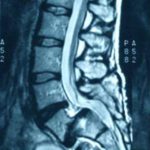

Brenda mora em Zortéa. Ela apresentava um problema grave na coluna e corria o risco de perder os movimentos da cintura para baixo. Brenda possuia espondilolistese lombar, conhecida como síndrome da cauda equina.

Conforme Sidnei o problema teria sido de nascença. O diagnóstico ocorreu durante uma consulta feita em Porto Alegre/RS. Os exames confirmaram a presença da espondilolistese lombar.

A partir daí a família correu contra o relógio. Brenda já estava no grau 3, avançando para o 4, numa escala que vai até cinco. Ela cansava as pernas rapidamente e não conseguia ficar muito tempo em pé. Continuou indo à escola [Horizonte Núcleo I], que fica perto de casa, mas no educandário precisava usar cadeira de rodas, e no retorno, o transporte escolar deixava a jovem na porta de casa para evitar que fizesse esforço físico.